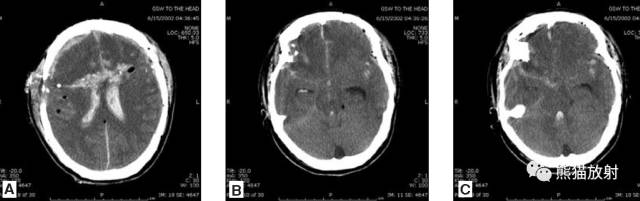

头部枪伤:可见*弹子**轨迹,穿越大脑中线,其毁灭性后果导致:侧脑室积血,蛛网膜下腔出血,脑积水(侧脑室颞角扩大),小脑幕疝(脑干周围基底池消失或不对称)。